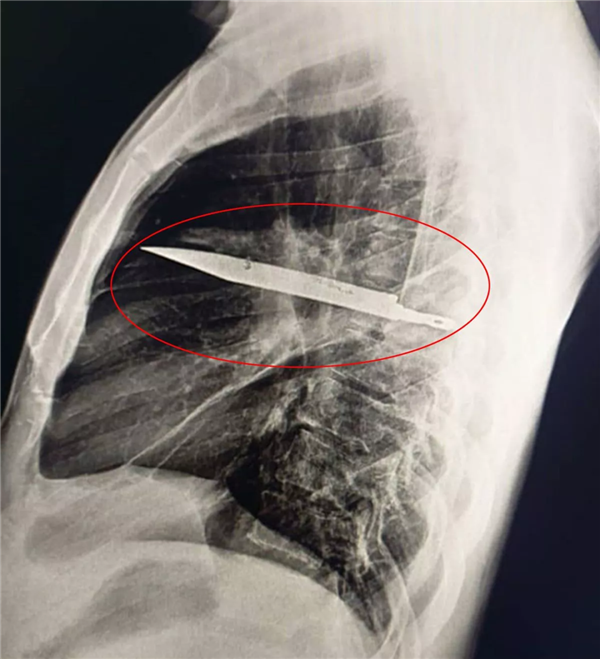

前段时间,《国家医学图书馆》发表了一个惊悚的案例,非洲坦桑尼亚一名44岁男子因为右胸疼痛流脓去医院看病,结果发现在他体内“藏着”一把刀。

就这样,这把刀从右肩胛骨刺入,完美避开体内重要的器官,然后一直隐藏在男子身体里,长达8年。

直到现在异物周围的组织坏死流脓,医生拍了 X 光,才发现“病灶”。

之后医生将刀取出后,男子很快就出院了,恢复很不错,在随后的采访中,男子依然很健康。